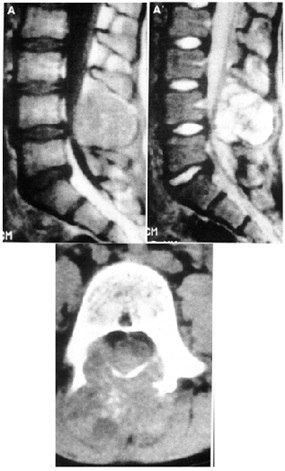

MRI and CT showed fluid in the bone (Figure. 2). Arthroscopic curettage without bone grafting was performed. A 6-mm skin incision was used to aspirate the bloody fluid and remove the cyst membrane (Figure 3). Pathologic examination demonstrated the cyst to be an ABC (Figure. 4). Curettage was performed using the arthroscope. Range of motion exercices were begun on the first postoperative day. The outcome was good and there was no evidence of recurrence at the 20-month follow-up (Figure. 5).

Figure 2: MRI and CT before surgery showing osteolysis and fluid in the bone.

Figure 5: MRI 20 months after surgery showing good bone formation.